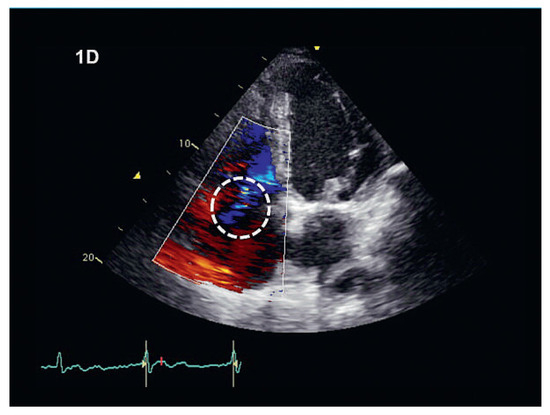

The differential diagnosis of systolic flow reversal includes tricuspid regurgitation (excluded in fig. 1D, dashed circle) as well as rhythm disorders (atrial or ventricular premature beats, atrioventricular block of any degree and atrioventricular dissociation during ventricular tachycardia).

Figure 1D. Colour-Doppler image. Relevant tricospid regurgitation can be excluded.